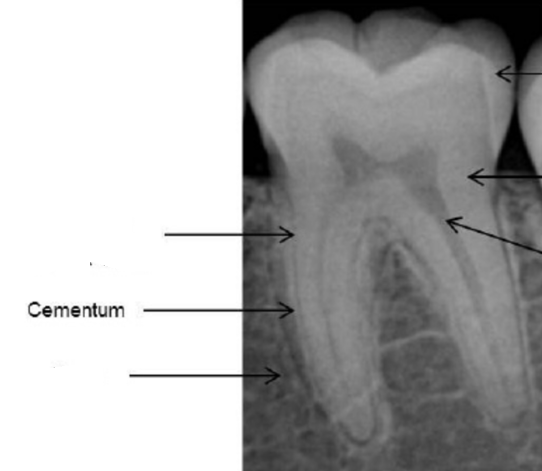

cementum

radiopaque

dentin

lamina dura

alveolar bone proper